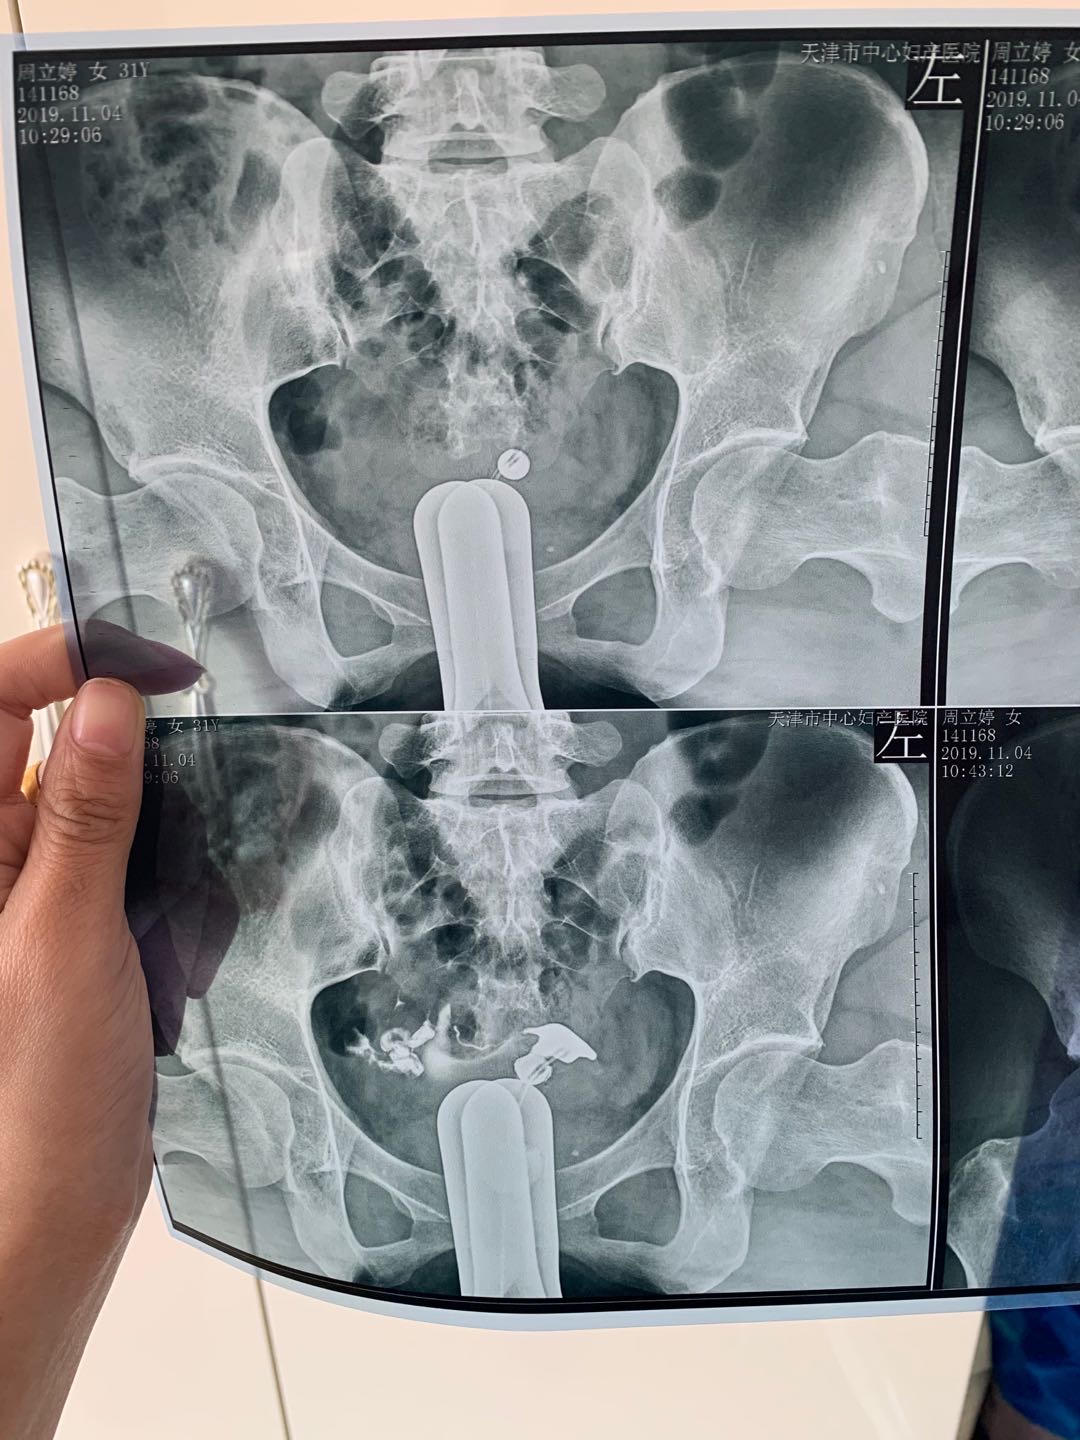

我今年34岁,右侧输卵管粘连,左侧宫外孕输卵

做完输卵管造影第六天了小腹还是感觉沉甸甸的如